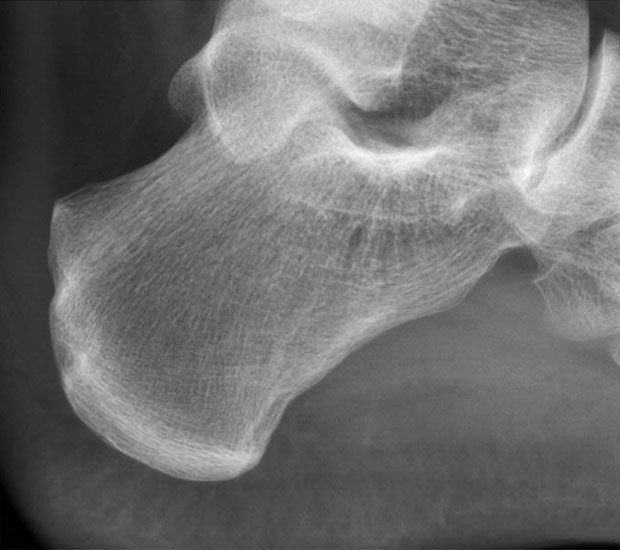

• Seitliches Röntgenbild der Ferse.

Abbildung 11-12

Prä- und postoperatives Röntgenbild.